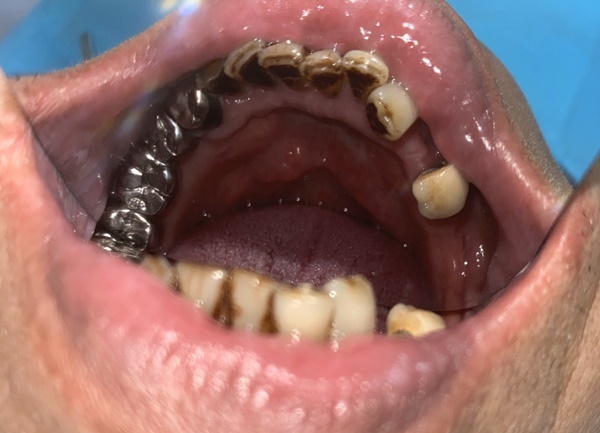

植牙醫師幫阿公先做了一遍牙齒清潔,想當然一定超快,阿公也沒幾顆可以檢查哈哈,植牙醫師便跟我們三個說:「爺爺剩下的牙齒照顧得還不錯,但也的確剩沒幾顆,這邊會建議做全口植牙或是活動假牙跟植牙搭配會比較有保障使用上老人家也會穩固方便許多,但還是看你們的選擇哦~」